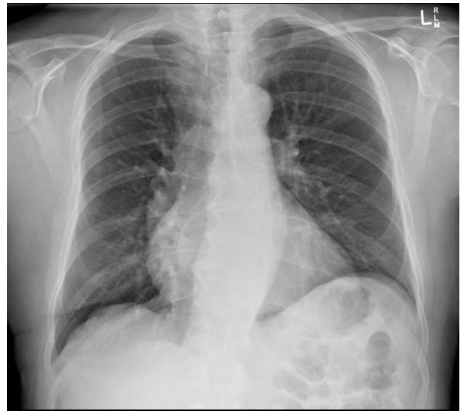

Qual das seguintes patologias abaixo estaria mais relacionada aos achados da seguinte radiografia de tórax?

Enunciado 3413094-1